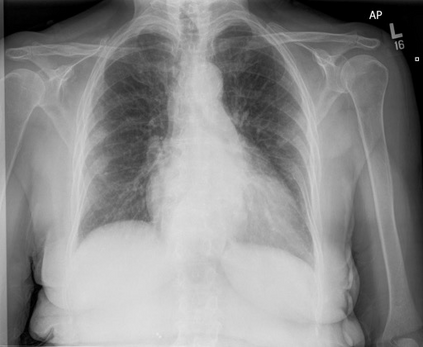

To address these issues, we propose a novel Adaptive patch-word Matching (AdaMatch) model to correlate chest X-ray (CXR) image regions with words in medical reports and apply it to CXR-report generation to provide explainability for the generation process. AdaMatch exploits the fine-grained relation between adaptive patches and words to provide explanations of specific image regions with corresponding words. To capture the abnormal regions of varying sizes and positions, we introduce the Adaptive Patch extraction (AdaPatch) module to acquire the adaptive patches for these regions adaptively. In order to provide explicit explainability for CXR-report generation task, we propose an AdaMatch-based bidirectional large language model for Cyclic CXR-report generation (AdaMatch-Cyclic). It employs the AdaMatch to obtain the keywords for CXR images and `keypatches' for medical reports as hints to guide CXR-report generation. Extensive experiments on two publicly available CXR datasets prove the effectiveness of our method and its superior performance to existing methods.